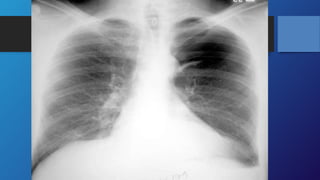

Investigations

Chest X-RAY is the diagnostic test in

most cases.

Investigations Chest X-RAY isthe diagnostic test in most cases.